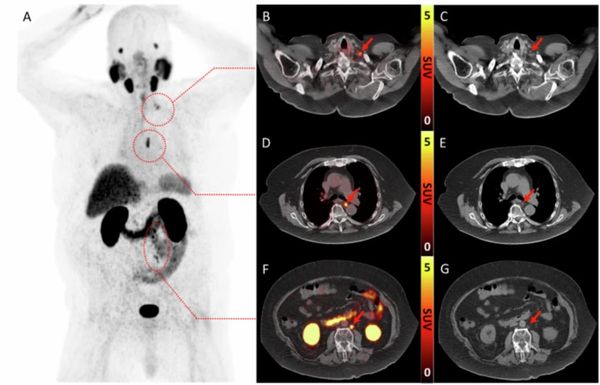

Nine Takeaways from New Review of PSMA PET/CT and Whole-Body MRI for Advanced Prostate Cancer

Catch up on the most-well viewed prostate cancer imaging content in October 2025.